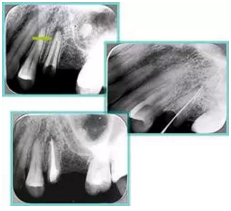

2. X 線片

共有 4 張 X 線片,分別是術(shù)前、診斷絲 、主牙膠尖確認(rèn)、術(shù)后。

( 1 )術(shù)前:術(shù)前 X 線片用來了解牙齒的大概情況。術(shù)前預(yù)期為多根牙時 X 線片應(yīng)偏頭拍攝。

( 2 )診斷絲:根據(jù)術(shù)前 X 線片進(jìn)行開髓、根管的初步預(yù)備后,需要插入診斷絲,用來指示工作器械位置。常用 10 號或 15 號擴(kuò)大器作為診斷絲插入牙髓腔。

( 3 )主牙膠尖確認(rèn):通過術(shù)前預(yù)期和診斷絲診斷,明確工作長度、牙根走向,進(jìn)行根管預(yù)備。之后應(yīng)進(jìn)行主牙膠尖(中銼)確認(rèn),已明確根管是否適合充填。

( 4 )術(shù)后:觀察治療效果。